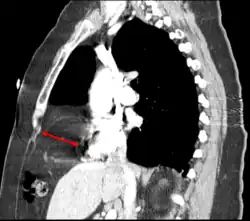

The Bochdalek hernia, also known as a postero-lateral diaphragmatic hernia, is the most common manifestation of CDH, accounting for more than 95% of cases. In this instance the diaphragm abnormality is characterized by a hole in the postero-lateral corner of the diaphragm which allows passage of the abdominal viscera into the chest cavity. The majority of Bochdalek hernias (80–85%) occur on the left side of the diaphragm, a large proportion of the remaining cases occur on the right side. To date, it carries a high mortality[3] and is an active area of clinical research.